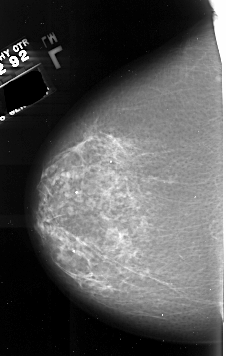

A_1008_1.LEFT_MLO

LEFT_MLO LINES 6556 PIXELS_PER_LINE 3796 BITS_PER_PIXEL 16 RESOLUTION 42 NON_OVERLAY